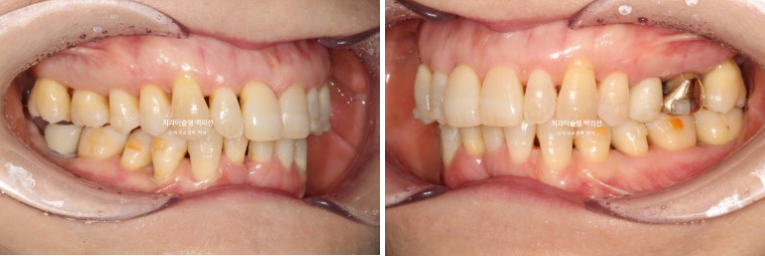

24.09~25.09

앞니가 깊게 물리는 과개교합이 개선되었습니다.

특히 뿌리가 보일 정도로 솟아내려와있던 파란 화살표 앞니가 건강하게 제 위치로 함입이 되고 노출된 뿌리 부분이 다시 잇몸속으로 안정적으로 들어갔습니다.

배열은 아주 깔끔합니다.

파란 화살표 치아가 치주염이 심해 발치한 치아입니다.